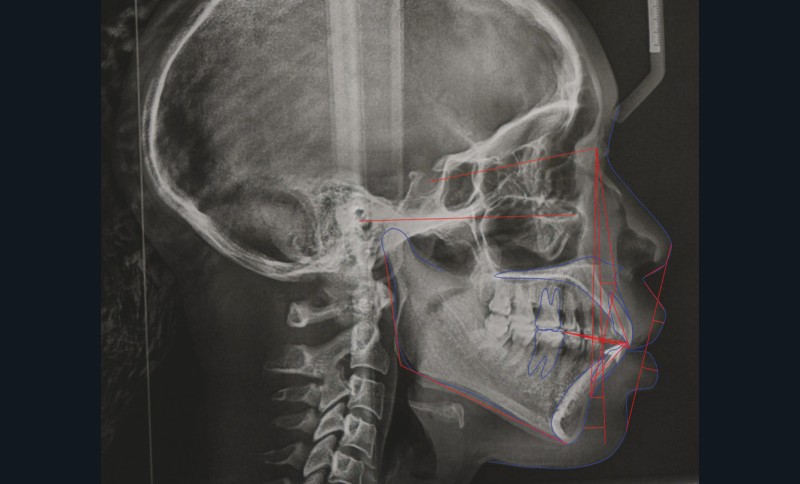

L’analyse céphalométrique de profil révèle des rapports de classe II de Ballard par prognathie maxillaire sur un schéma facial normodivergent associés à une forte proalvéolie mandibulaire (IMPA : 108°) et une légère retroalvéolie maxillaire (I/FH : 108°) (fig. 9 et 10).